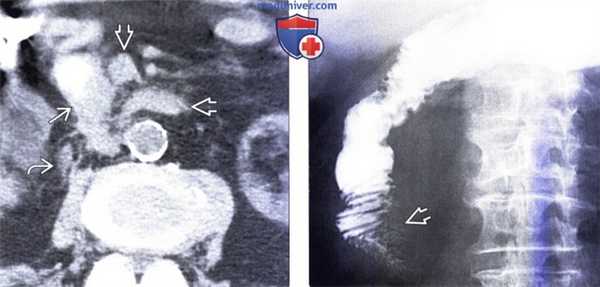

(Слева) На аксиальной КТ без контрастного усиления, выполненной мужчине 88 лет с жалобами на раннее насыщение и снижение веса тела, определяется растянутый желудок (не показан на представленном срезе). Определяется внезапное, эксцентрическое сужение просвета второй части двенадцатиперстной кишки. Опухоль распространяется, инфильтрируя расположенную поблизости жировую клетчатку, кроме того, имеет место регионарная лимфаденопатия.

(Справа) На рентгенограмме, полученной при рентгеноскопии верхних отделов ЖКТ у этого же пациента, определяется выраженная обструкция второй части двенадцатиперстной кишки, обусловленная скиррозным образованием, представляющим собою первичный рак.г) Патология: